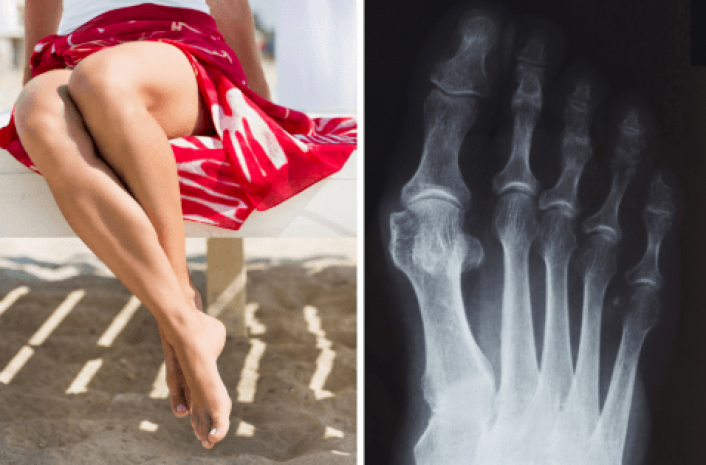

Болезненная деформация стопы — выпирающая косточка на большом пальце ноги — проблема, которая знакома многим женщинам, сообщает woman.ru.

То, что в обиходе мы называем косточкой на большом пальце ноги, на научном языке звучит как вальгусная деформация пальца стопы. Никакой «шишки» на ноге нет. Это только так кажется. На самом деле – это отклонение первой плюсневой кости стопы во внутреннюю сторону с одновременным наклонением большого пальца к наружней стороне. Если на проблему сразу не обратить внимание, то ситуация со временем только ухудшится. Постепенно косточка будет все сильнее выпирать. Это не только уродует ногу, но и причиняет сильную боль при ходьбе. А кроме того создает невероятные трудности при выборе обуви.

Бывает, что косточку на большом пальце ноги принимают за артроз, подагру или отложение солей. Поставить диагноз может только врач-ортопед на основании визуального осмотра и рентгена стоп, а также анализа крови.